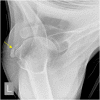

The rotator cuff is a group of four muscles and tendons surrounding the shoulder joint providing it strength and stability. The rotator cuff consists of the subscapularis, supraspinatus, infraspinatus and teres minor. Many shoulder complaints are caused by rotator cuff pathology such as impingement syndrome, tendon tears and other diseases e.g. calcific tendonitis. Diagnosis starts with clinical history and physical examination, after which imaging is often used to help confirm clinical findings depending on the differential diagnosis. The aim of the article is to review the frequently used imaging modalities to assess the rotator cuff and cuff-related disease, specifically focusing on radiography, ultrasonography and magnetic resonance imaging. This article will outline the advantages and disadvantages for each modality and illustrate typical radiological findings of common rotator cuff pathologies.